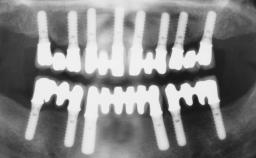

Conventional Loading of Six Implants in the Mandible and Final Restoration with a Full-Arch Metal-Ceramic FDP

# of Implants 6

Type of Implants One-Piece

Surgical SAC classification

SAC Level Advanced

Defining Characteristics Fully edentulous lower jaw to be rehabilitated with two or more implants

Modality > 4 implants, extending to mental nerve region

Prosthodontic SAC classification

SAC Level Complex

Defining Characteristics Fully edentulous lower jaw to be rehabilitated with an implant-borne fixed dental prosthesis

Retention Screw-retained, with 4 or more splinted implants Screw-retained, with 4 or more splinted implants